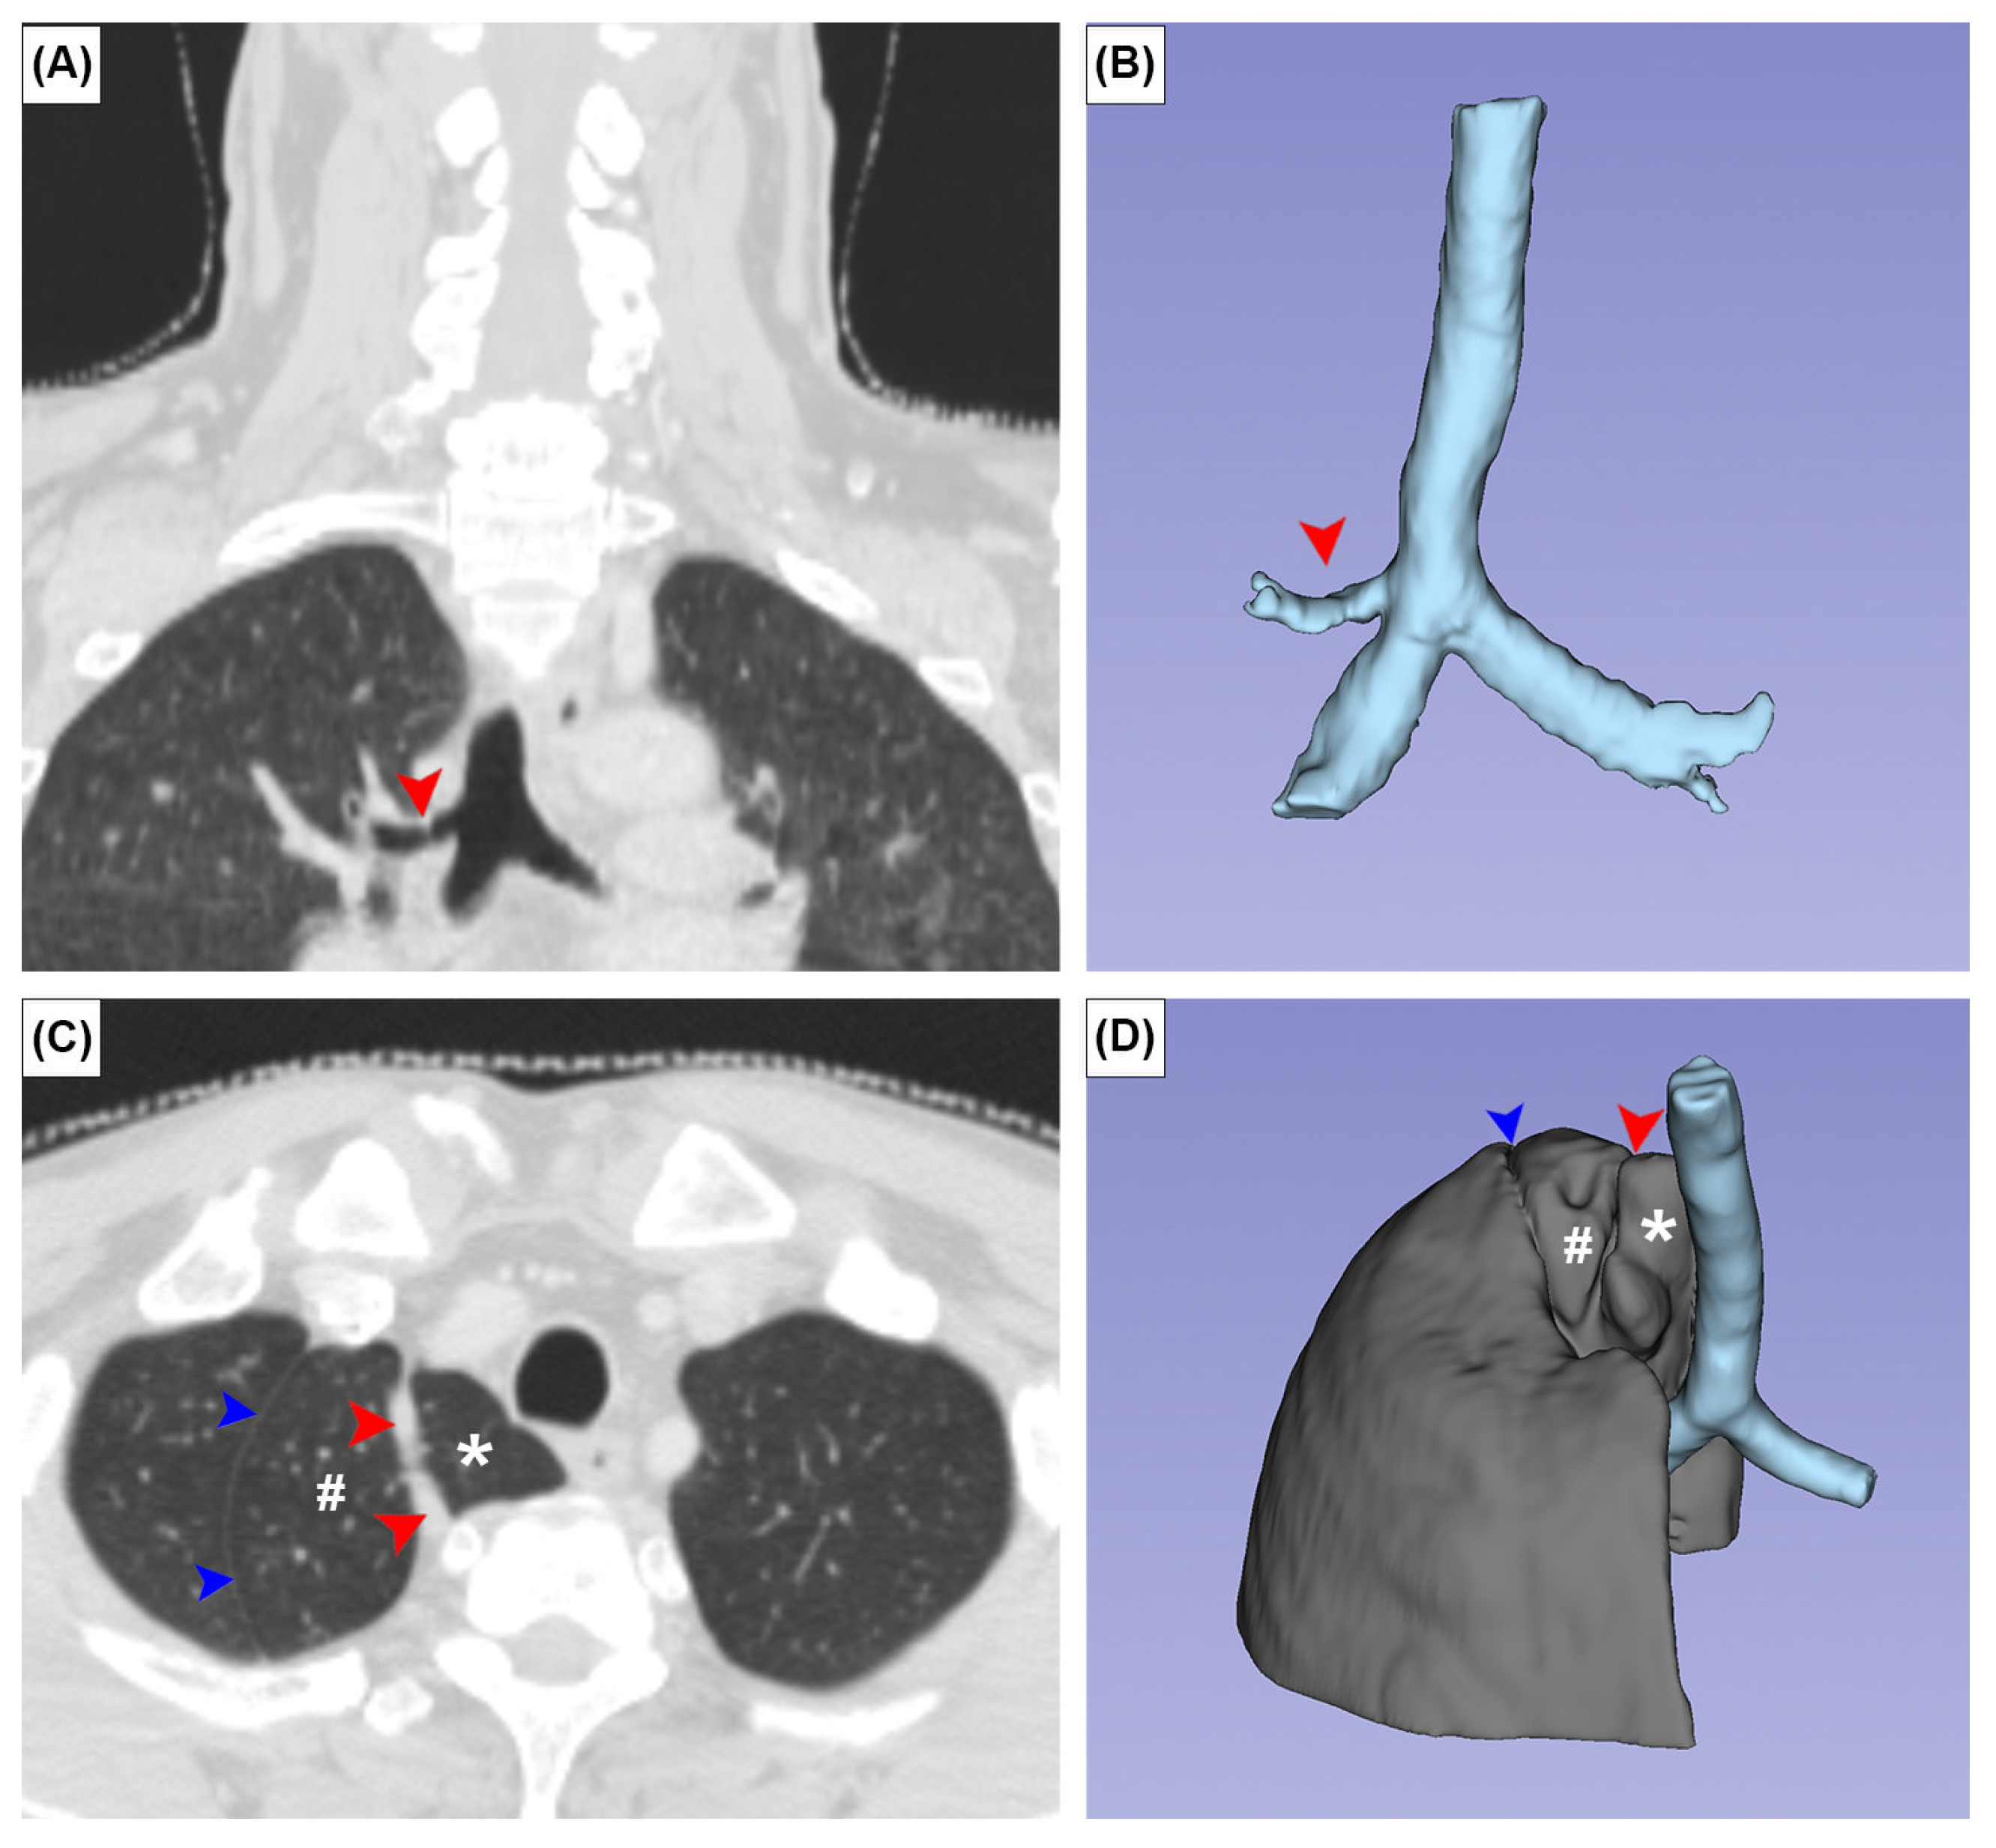

The TB and AL were observed in three (0.5%) and two (0.3%) patients, respectively. In all TB cases, the TB supplied the apical segment of the superior lobe of the right lung. No SBC was observed in any patient (Figure 4A,B). In one patient with an AL, the superior lobe of the right lung was unusually small and the anterior margin of the oblique fissure was located aberrantly superior (Figure 4C,D). There was a statistically significant sex difference in CR prevalence (p = 0.05). No significant sex differences were found for other variants (Table 1).

Two bronchopulmonary variants were studied: the AL and TB. There was an AL, or accessory lobe of the superior lobe of the right lung, in 0.3% of cases in this study. This is identical to the average prevalence of 0.3% reported in a recent meta-analysis [14]. In one of our two cases, the AL was accompanied by a superiorly placed oblique fissure, which downsized the superior lobe of the right lung (Figure 4C,D). This variant oblique fissure should not be confused with an azygos fissure, because no azygos vein was found in it. The AL is nine times more common in people with congenital abnormalities, suggesting that its presence is genetically mediated [14]. It is currently accepted that the AL is formed when the azygos vein precursor migrates to its usual position through, rather than medial to, the apex of the right lung [35]. The appearance of an AL on a CT can be mistaken for an abscess, bulla, or pneumothorax [36]. The TB, found in 0.5% of cases in this study, represents an accessory bronchus that originates superior to the tracheal bifurcation. It usually gives rise to the apical bronchopulmonary segment of the superior lobe of the right lung. Three hypotheses have been proposed to explain its formation: reduction of a previously developed bronchus, migration of part of the developed hyparterial branching pattern to a different location, either on the trachea or a bronchus, and local morphogenesis [37]. A meta-analysis reported that the overall prevalence of TB was 1.0% [15]. Similar to the AL, the TB was 15 times more common (14.9%) in individuals with congenital anomalies, which suggests that TB occurrence may be influenced by genetics.

Figure 4. Coronal (A,C) CT images and three-dimensional images of the tracheal bronchus (A,B) and azygos lobe (C,D). Red arrowheads and asterisks indicate the azygos fissure and azygos vein, respectively. Blue arrowheads and # indicate a variant placement of the oblique fissure and unusually small superior lobe of the right lung.